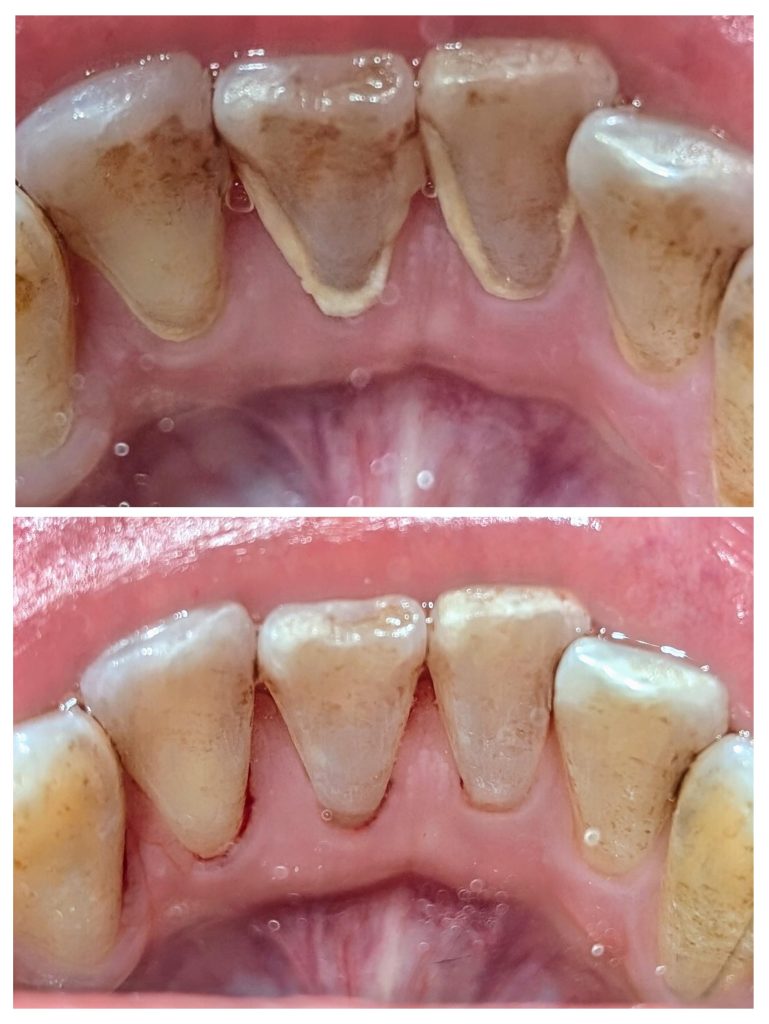

ANBIシドニーでは、ほとんどの治療にマイクロスコープを活用。

肉眼では見えない歯石や汚れをしっかり捉え、

歯茎に優しい

痛みが極めて少ない

効果が長持ち

という、ワンランク上のクリーニングを可能にしています。

これは一般的なクリニックではまだ珍しい“高度機器”。

せっかくシドニーでケアするなら、“精密ケア”できれいに、そして長く健康に。

毎日のコーヒー、紅茶、ワイン、喫煙…

歯磨きでは落ちない頑固な汚れは、口臭の原因にも。

ホワイトニングではありません。

プロのスケーリングだけで、この輝き。

舌で触れた時の“キュッ、ツルッ”とした感覚は感動ものです。

「歯石取り=痛い」というイメージ。

ANBIではその概念を覆します。

繊細な日本人の感覚に合わせた調整

超音波機器と手用器具の最適な使い分け

必要であれば表面麻酔も対応

“痛みの少ない治療”にこだわり続けるのは、開院22年以上の経験と技術があるからこそ。